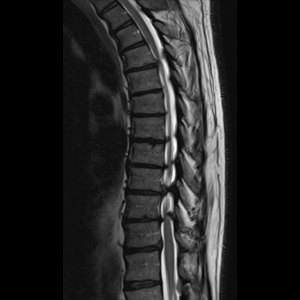

Spinal stenosis (Lumbar) Spinal stenosis (Cervical) Spinal stenosis (Thoracic) Lumbar Disc Herniation Spondylolisthesis Cervical Foraminal Stenosis Vertebroplasty Lumbar Fusion Anterior Cervical Fusion (ACDF) Posterior Cervical Fusion Thoracic Fusion Revision Lumbar Fusion Surgery Facet Joint Cyst Spinal Tumour Minimally Invasive Lumbar Fusion (XLIF) Minimally Invasive Lumbar Fusion (ALIF) Lumbar Fusion (TLIF) Thoraco-lumbar Fusion Lumbar Corpectomy Complex Lumbar Spine Surgery (Spino-pelvic fixation) Complex Cervical Spine Surgery Complex Thoracic Spine Surgery Occipito-cervical Fusion Minimally invasive surgery for thoracic disc herniation Other Related Topics